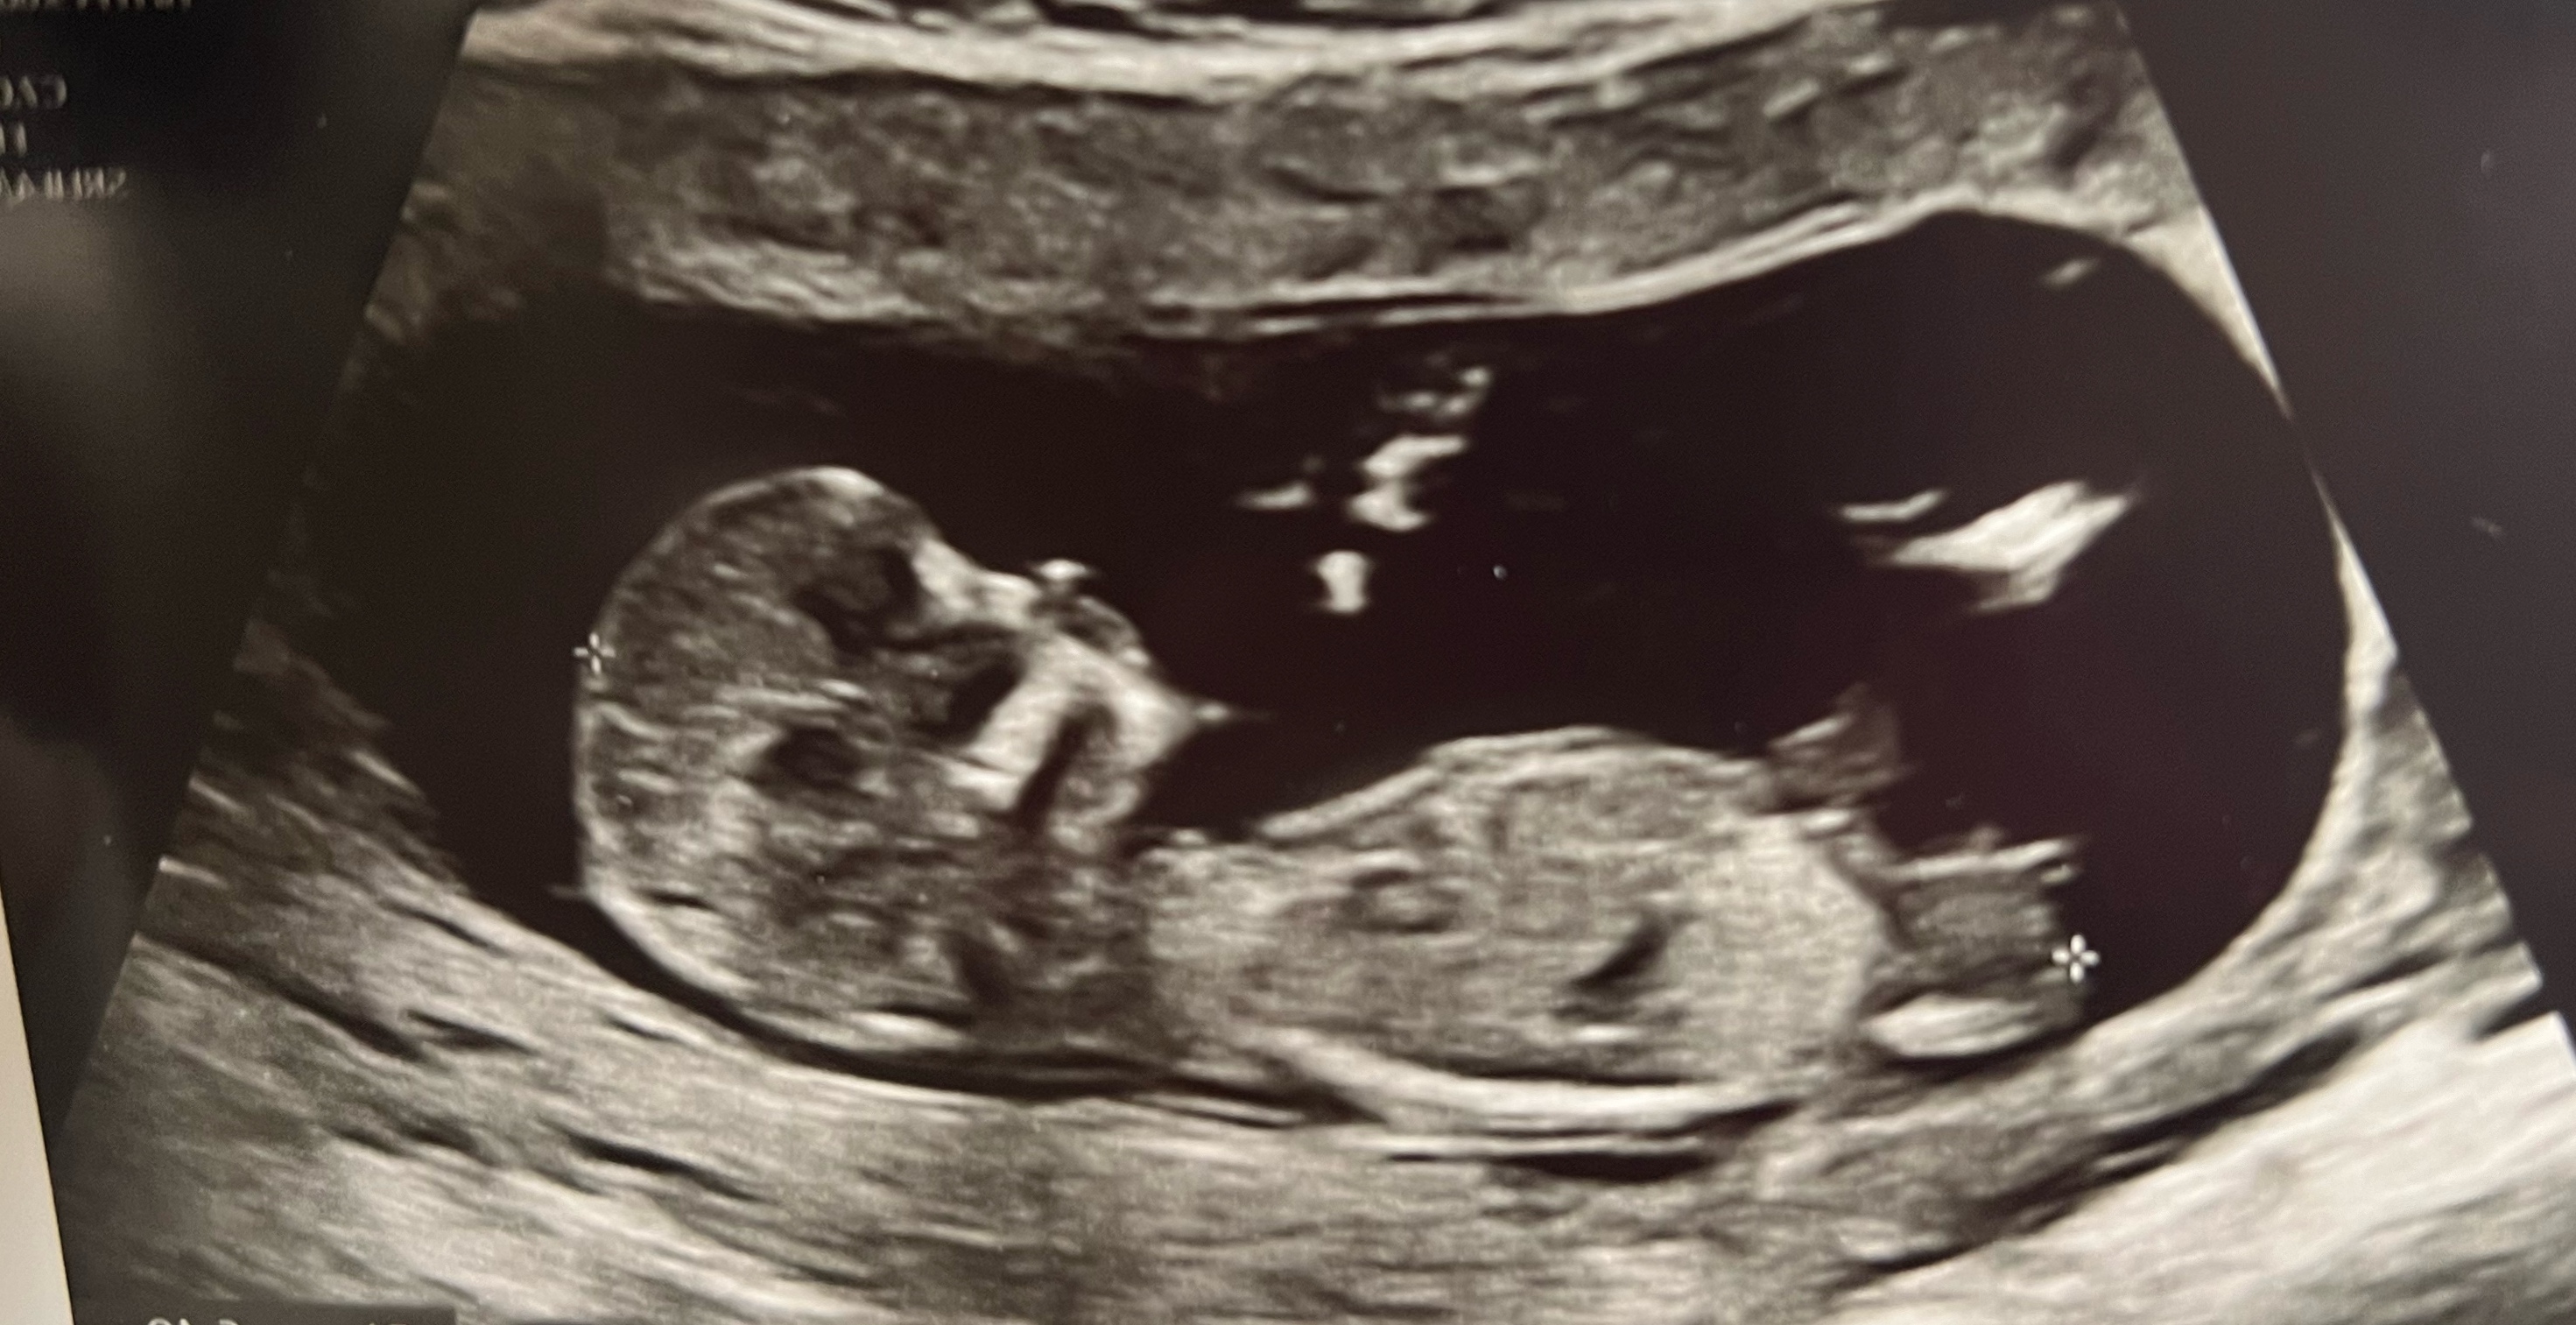

Witam serdecznie, byłam wczoraj na prenatalnych , czy widać tutaj płeć ?

Załączniki

• IMG_20240516_090140.jpg

IMG_20240516_090140.jpg

1,1 MB · Wyświetleń: 222

• IMG_20240516_090330.jpg

IMG_20240516_090330.jpg

141 KB · Wyświetleń: 232